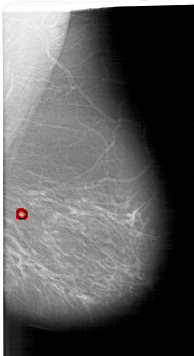

FILE: A_1349_1.RIGHT_MLO.OVERLAY

TOTAL_ABNORMALITIES 1

ABNORMALITY 1

LESION_TYPE CALCIFICATION TYPE PLEOMORPHIC DISTRIBUTION SEGMENTAL

ASSESSMENT 4

SUBTLETY 4

PATHOLOGY BENIGN

TOTAL_OUTLINES 2

BOUNDARY